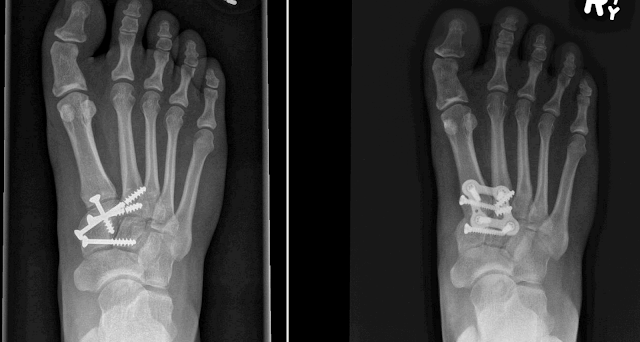

Lisfranc / Midfoot fusion - pre and post-op x-ray montage / Lisfranc and Ligamentous Lisfranc injuries

Some recent cases completed at Georgetown Hospital:

Case 1:

Case 2: